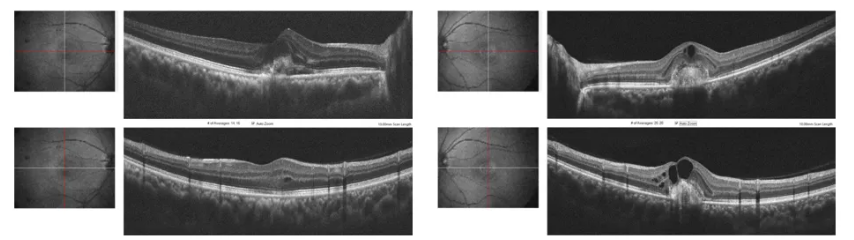

病例一:长期误诊为CSC的双眼PCV

患者为一名44岁男性,因“左眼视力下降1年余”就诊,否认全身特殊慢性病史。右眼曾于2011年10月(患者37岁)诊断为“CSC”,接受半量PDT治疗;左眼于2017年12月(患者43岁)诊断为“CSC”,接受半量PDT治疗。

OCT+OCTA

复诊:患者回家观察5个月后复诊,诉左眼视力无提高。

眼科检查见右眼情况趋于稳定,黄斑区结构上较半年前似乎变化不大,但是仍然可见扩张的Haller层及增厚的脉络膜表现。然而左眼可见多处色素上皮改变,其中绿圈、绿箭处可见似指状突起的改变,其间似乎可见少许血流信号。

为明确患者是否是长期CSC合并CNV形成,进一步检查病灶变化,行FFA+ICGA检查。

右眼造影全程皆为静止性病灶;左眼ICGA早期看到了BVN和扩张的息肉样改变,随时间延长,囊样扩张的息肉呈现“冲刷现象”。同时,造影影像中伴有脉络膜血管高渗透性改变。

回顾早期的录像,确实发现PCV的影像改变。

ICGA与OCTA结合

观察到血管侵入了RPE和Bruch膜与内脉络膜之间的空间,并向上推动RPE。

思考:患者是长期CSC转化为PCV吗?还是一开始就是PCV?

为了弄清楚这个问题,李燕教授团队追问患者详细病史及检查其既往检查资料,发现既往右眼初次发病的ICGA资料提示,右眼初次发病已出现PCV病理改变(绿箭:BVN,红箭:息肉)。同时,造影影像中伴有脉络膜血管高渗透性改变。

患者左眼发病后,李燕教授团队意识到,该患者原来一开始就是PCV。患者初次右眼发病,年龄为37岁,这相较于通常PCV患者的发病年龄较年轻。右眼已经是陈旧性病灶且无活动性改变,考虑观察;左眼给予球内注药治疗(3针后),但患者后续并未按时复诊。

诊断:双眼PCV(左眼活动性)

治疗:左眼玻璃体腔内注射抗VEGF药物(每月1针,连续3月)。